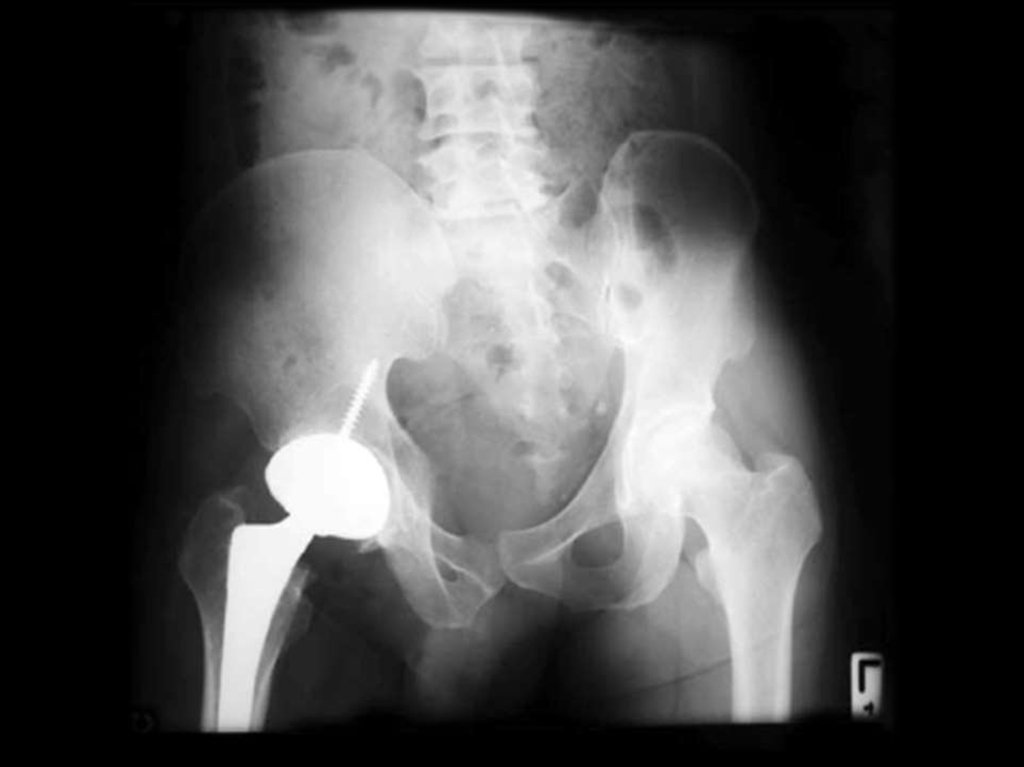

Артроз ТБС

Постепенно нарастающая боль в паху

и в

области таза или ослабление мышечносвязочного аппарата и появление слабости в

ногах (“ноги не идут”).

В дальнейшем – усиление или появление боли

при отведении и внутренней ротации бедра,

затем при всех движениях и, наконец, сустав

может полностью фиксироваться в положении

сгибания и наружной ротации.

На поздних стадиях боль очень сильная и

мучительная, отмечается хромота и “утиная

походка”.